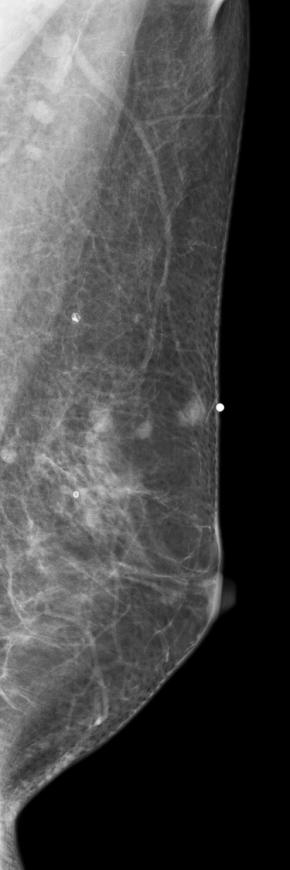

[355,Breast] 61/F,A palpable mass in the left breast

Breast

Modality

US,Etc,

What is your diagnosis?